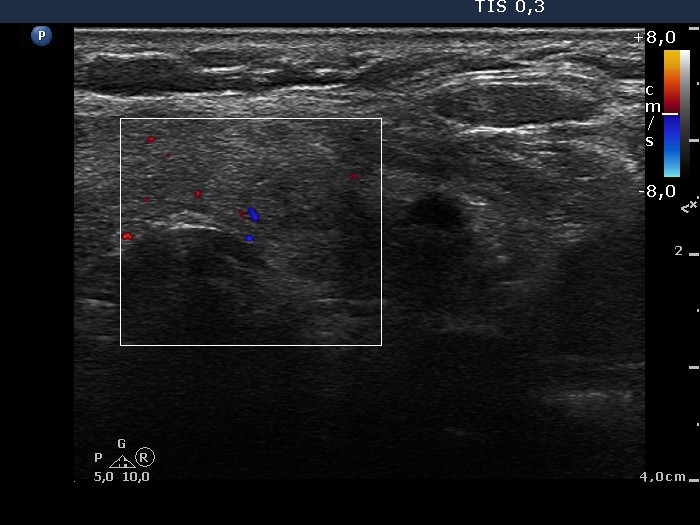

Lower part of the left lobe, transverse scan, color Doppler mode.